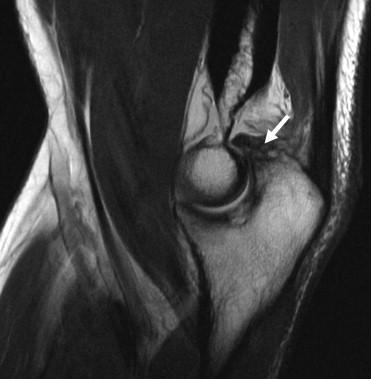

A 20-year-old man sustained an injury to his arm during a tug-of-war contest. An MRI scan is shown in Figure 1. What is the most likely diagnosis?

The MRI scan reveals a transection of the biceps muscle. The underlying brachialis is intact. This injury can occur as a result of a cord wrapped around the upper arm. Care should be taken to ensure that there is no concurrent vascular injury.